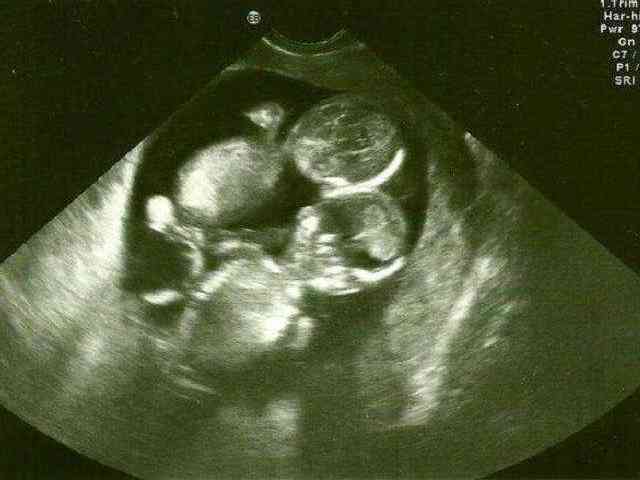

如果两个胚胎到了女性子宫内同时存活,而且状态良好,关键是女方的身体情况,适合孕育双胞胎,且平稳度过了孕期顺利分娩,这样才有了试管婴儿双胞胎的诞生,相对来说试管婴儿怀双胞胎的几率要高于自然受孕,但并不是每个人做试管都能生双胞胎。